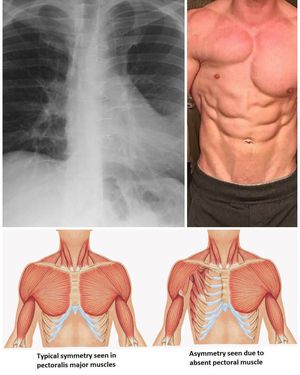

Seen here is a clinical picture and radiography of the chest showing poland's syndrome most common manifestation which is the absence of pectoralis muscles. Poland syndrome is a congenital defect in which there is hypoplasia or aplasia of pectoralis muscle most commonly major followed by minor, ipsilateral 2nd to 5th ribs, or ipsilateral breast or nipple. Other clinical manifestations include small hand and brachysyndactyly, simian crease of affected extremity. The condition is benign and depending on the degree of involvement of the upper extremity may be asymptomatic. Cosmetic reconstructive surgery may be considered (e.g. breast implant)